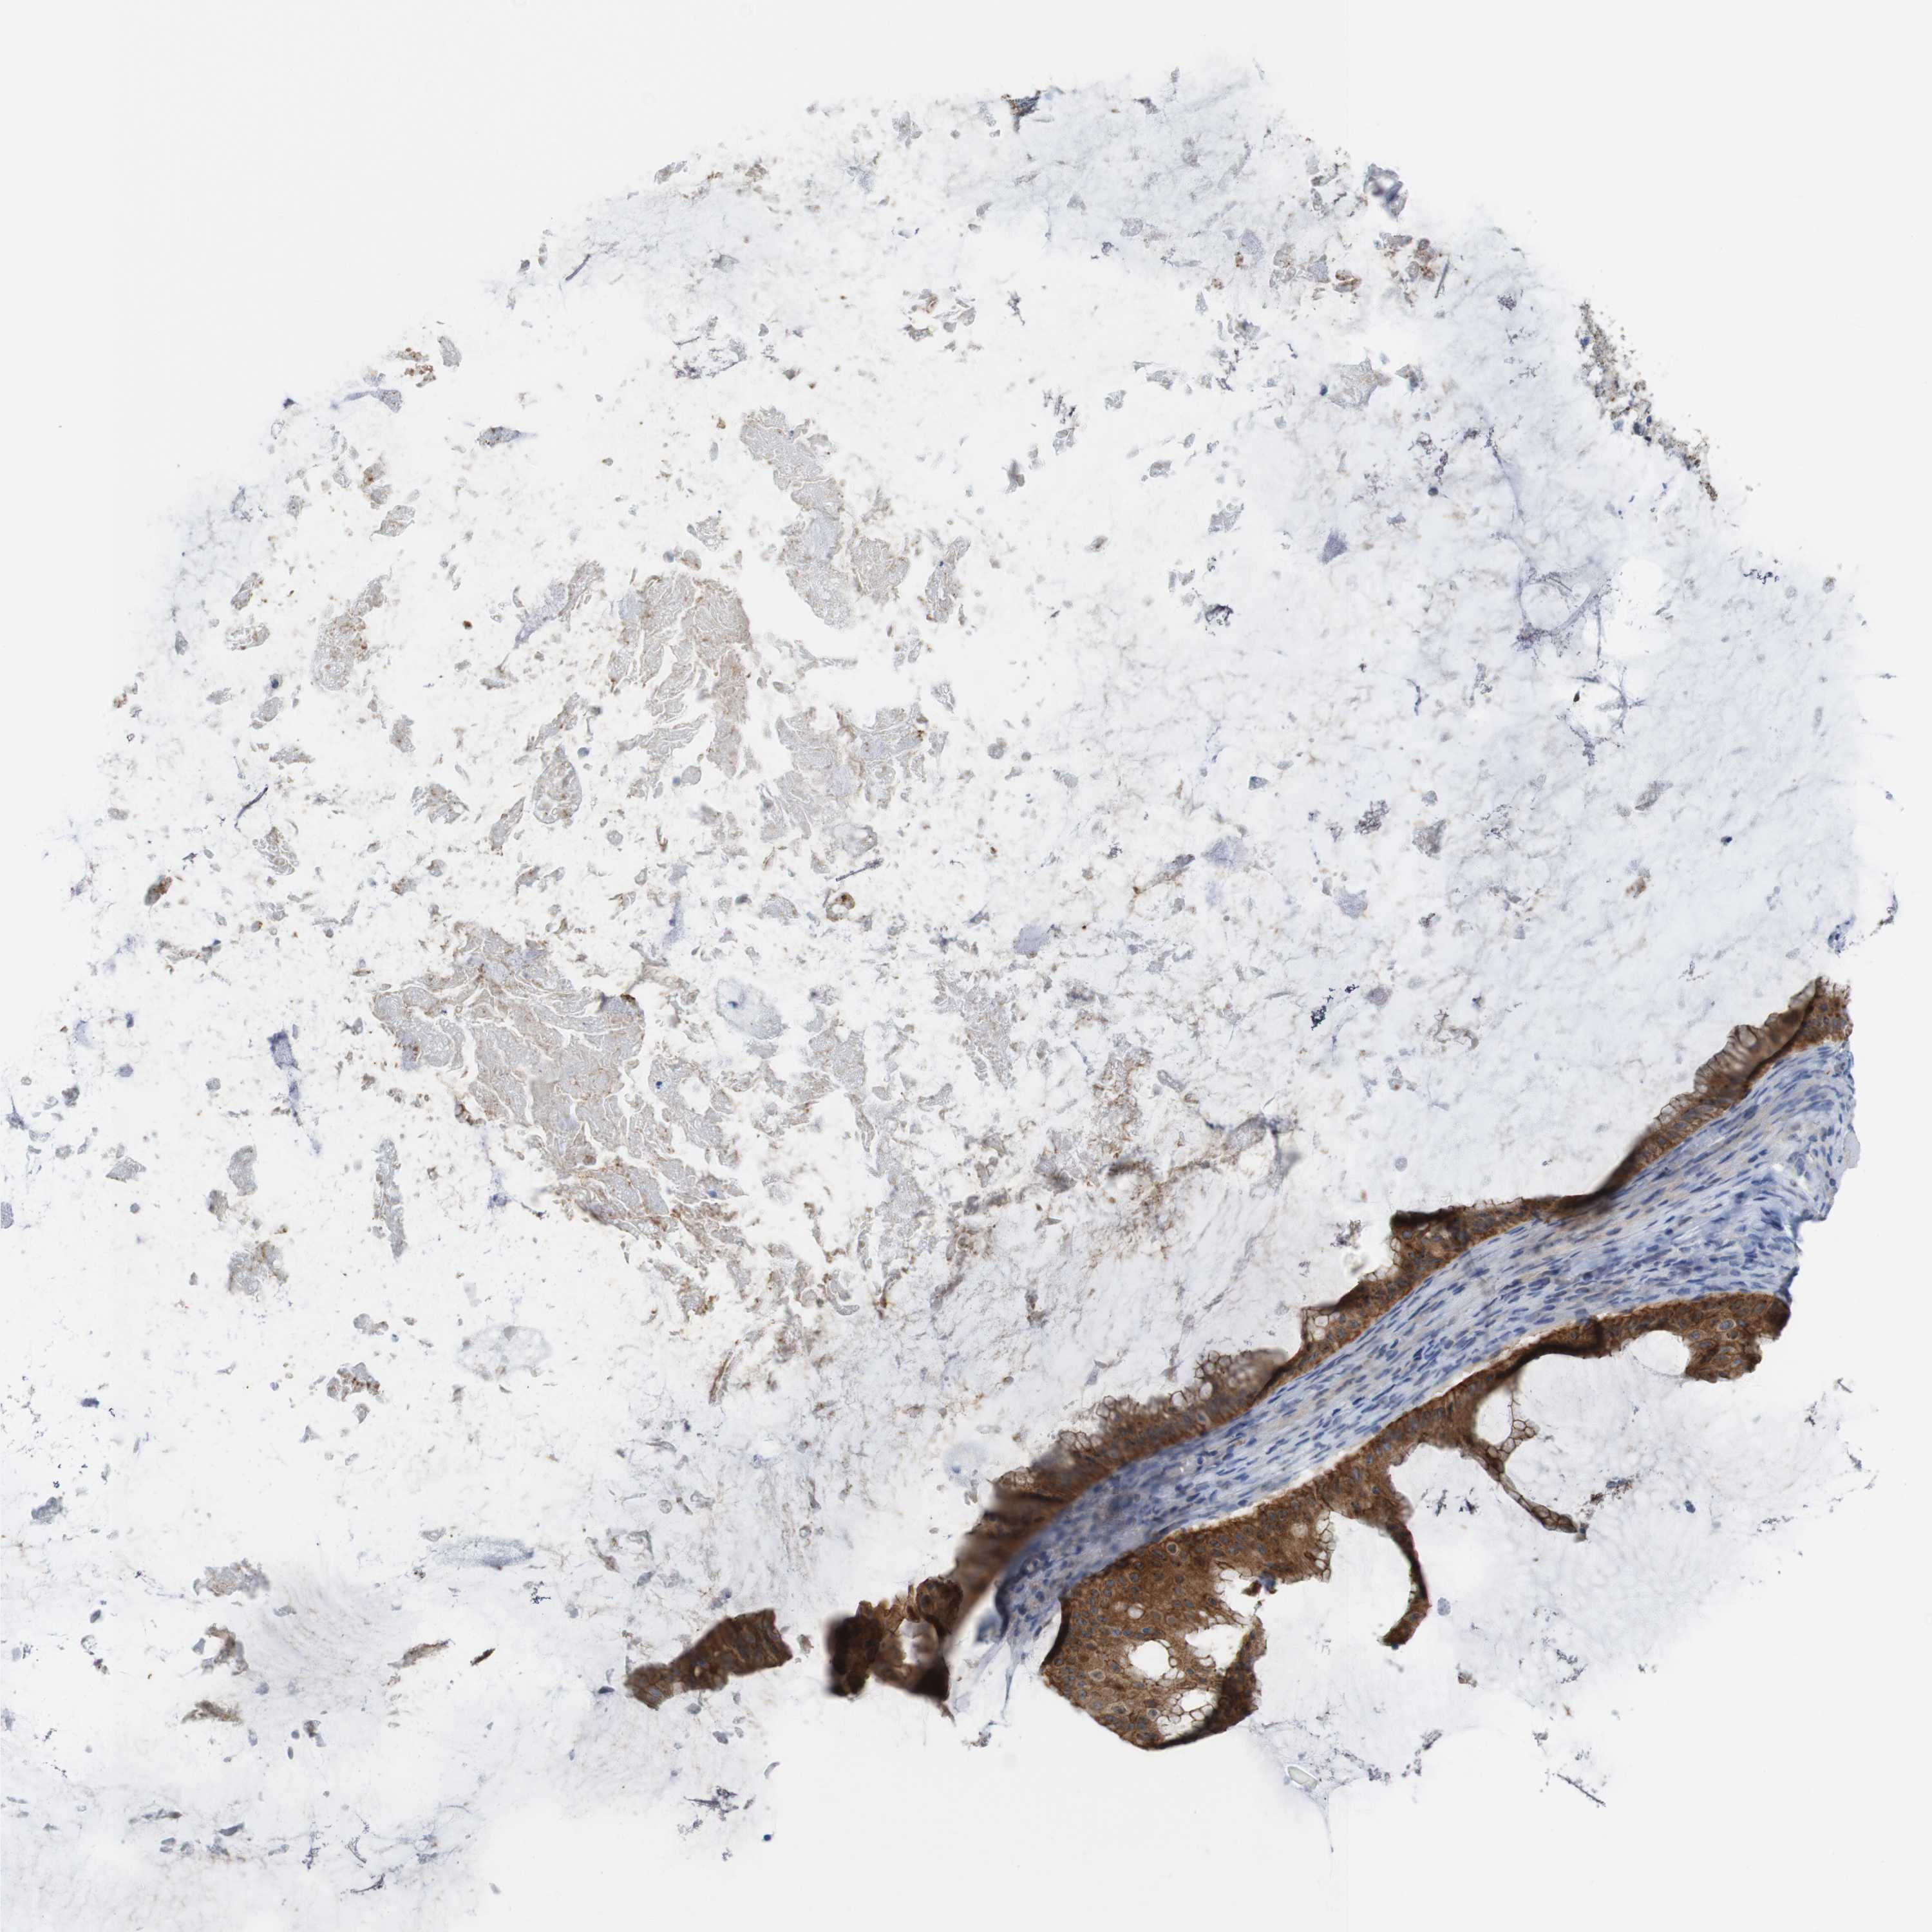

OVARIAN CANCER - Protein expressioni

A mouse-over function shows sample information and annotation data. Click on an image to view it in a full screen mode. Samples can be filtered based on level of antibody staining by selecting one or several of the following categories: high, medium, low and not detected. The assay and annotation is described here.

Note that samples used for immunohistochemistry by the Human Protein Atlas do not correspond to samples in the TCGA dataset.

Antibody stainingi

Antibody staining in the annotated cell types in the current human tissue is reported as not detected, low, medium, or high, based on conventional immunohistochemistry profiling in selected tissues. This score is based on the combination of the staining intensity and fraction of stained cells.

Each image is clickable and will lead to virtual microscopy that enables deeper exploration of all samples and also displays staining intensity scores, fraction scores and subcellular localization as well as patient and tissue information for each sample.

Antibody HPA053337

Antibody CAB013244

Cystadenocarcinoma, serous, NOS

Carcinoma, endometroid

Carcinoma, NOS